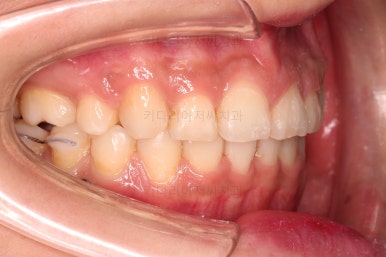

1. 초진

연산동교정치과 초진 시 입안의 모습입니다.

아랫니 어금니가 하나 없어서 주위 치아들이 해당 위치로 쓰러진 상태였습니다.

그리고 양쪽의 교합이 톱니바퀴처럼 맞물려 있는 것 같지만 톱니바퀴가 한 칸씩 밀려서 맞물려 있는 부정교합이 있는 상태였습니다.

장치를 부착했고요.

이번에 환자분이 선택한 장치는 윗니는 자가결찰 세라믹, 아랫니는 자가결찰 메탈이었습니다.

이렇게 혼용해서 사용해도 되는 조합들이 있고요.

이번 환자분은 웃을 때 이가 많이 보이는 타입이 아니셔서 아랫니는 좀 더 튼튼하고 저렴하기까지한 메탈장치를 선택하셨죠.